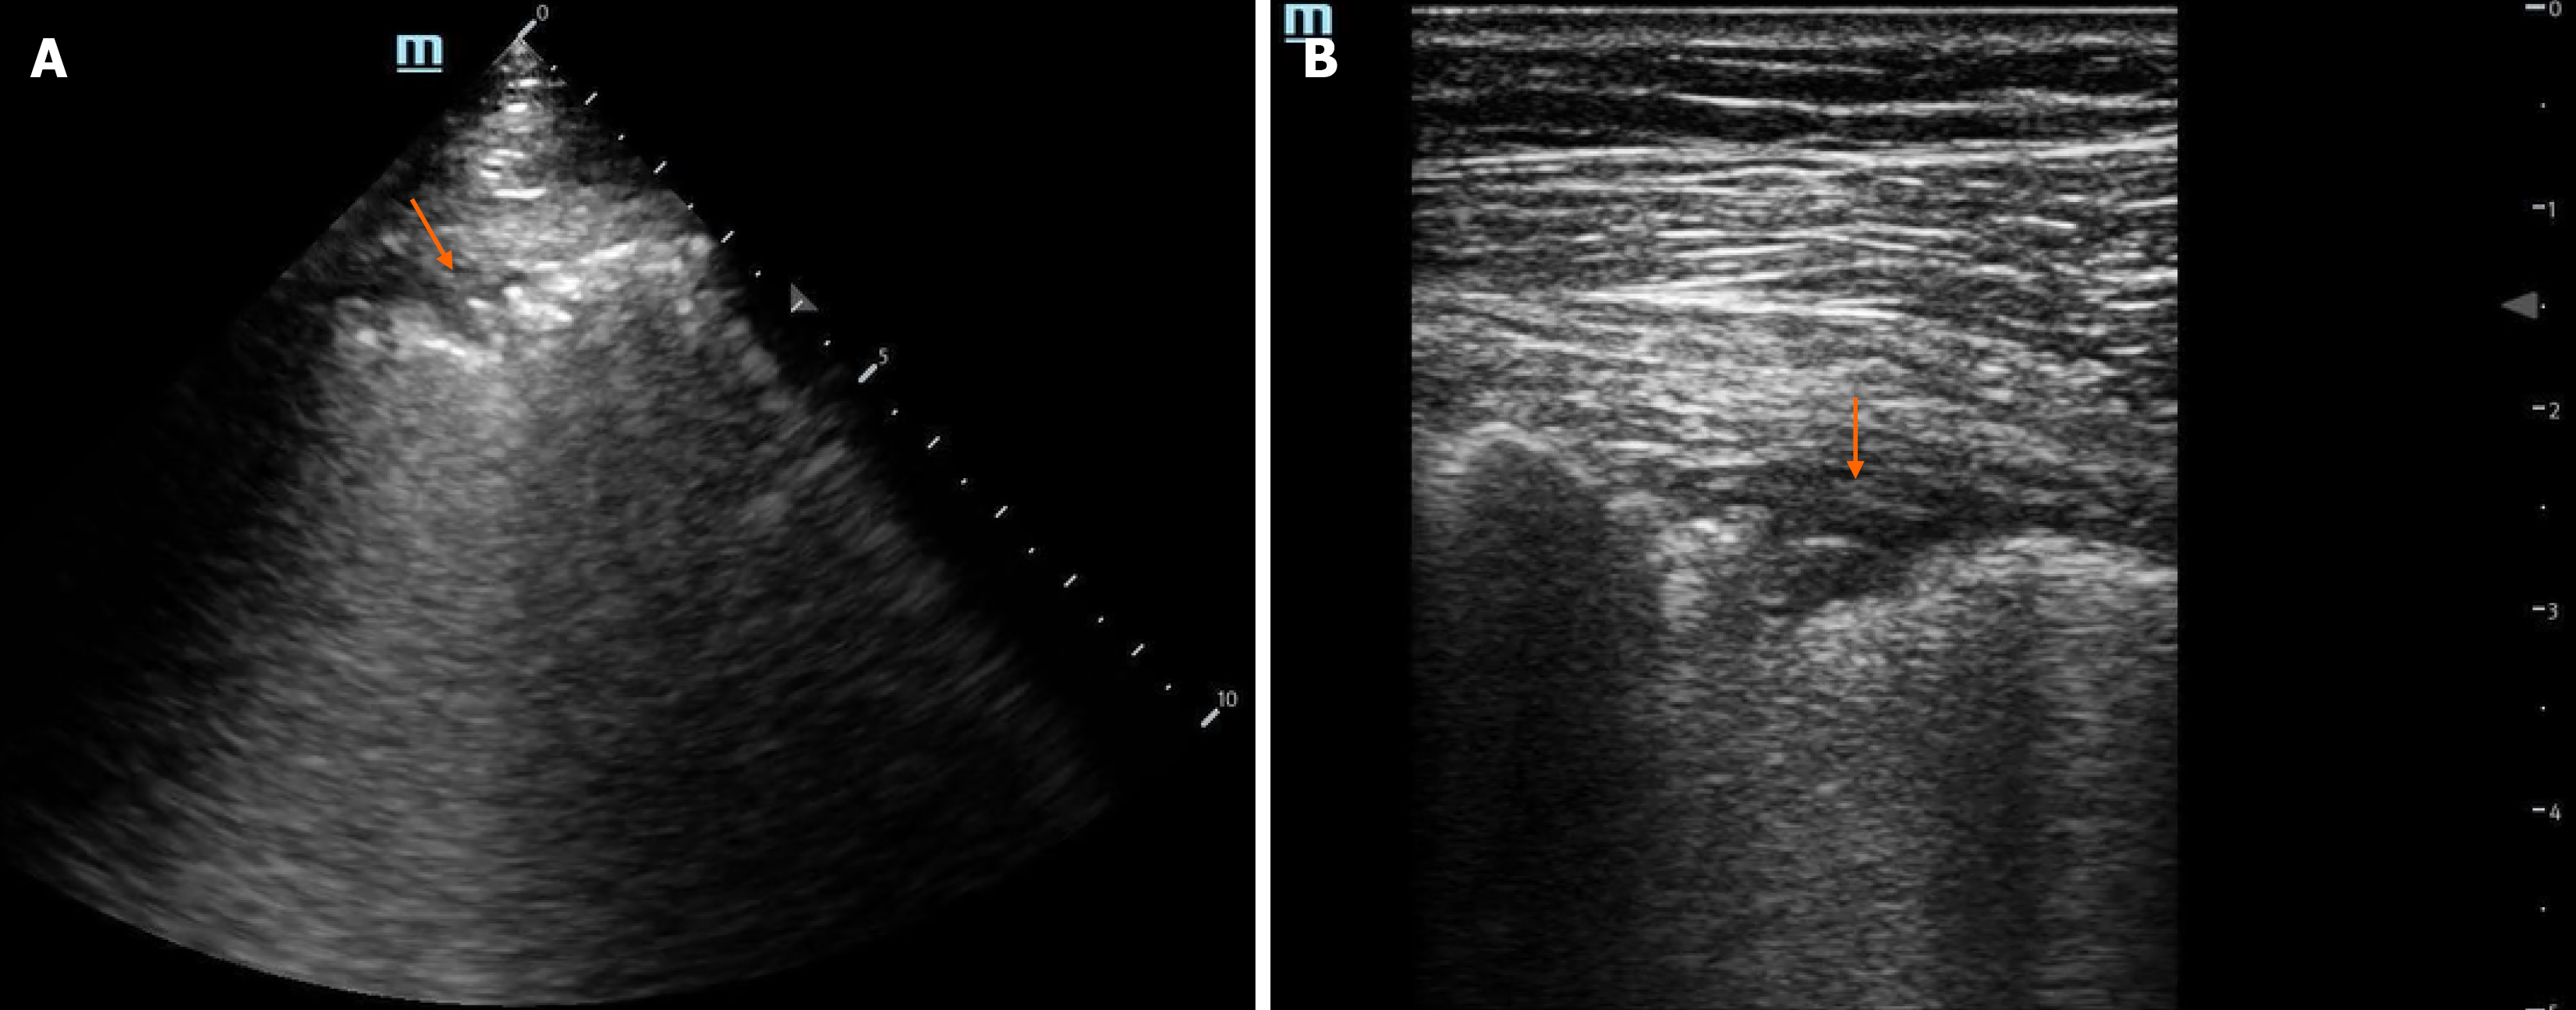

In everyday clinical practice, LUS typically uses an 8-zone scanning protocol, dividing each hemithorax into four zones based on key anatomical landmarks: The parasternal, anterior axillary, and posterior axillary lines, along with a horizontal line at the level of the third intercostal space. This creates eight zones in total - four on each side: Upper anterior, lower anterior, upper lateral, and basal lateral. These zones are strategically chosen, for instance, air rises, so pneumothorax is best assessed in the anterior zones, while dependent edema and pleural effusions are commonly detected in the lateral zones. Although this 8-zone protocol is commonly used, most published data in the ESRD population are based on the more comprehensive 28-zone approach. This method evaluates 16 intercostal spaces on the right and 12 on the left, with fewer zones on the left due to the heart’s position (Figure 1). It’s important to note that, unlike cross-sectional imaging like computed tomography, LUS cannot visualize the entire lung. Localized issues such as small consolidations or infarcts, as well as lesions that do not extend to the pleural surface, like masses, may be missed. That said, this zonal approach is generally sufficient for nephrology-related applications, particularly assessing extravascular lung water (EVLW)[14]. From an equipment standpoint, LUS can be performed using low-cost ultrasound machines, including handheld devices equipped with phased array or curvilinear transducers. Some handhelds also feature integrated all-in-one probes.

Figure 1

Figure 1 Lung ultrasound zones. A: Twenty-Eight-zone method: 16 intercostal spaces on the right and 12 on the left are examined; B: Eight-zone lung ultrasound: Four zones in left hemithorax. In this method, each zone may include more than one intercostal space.